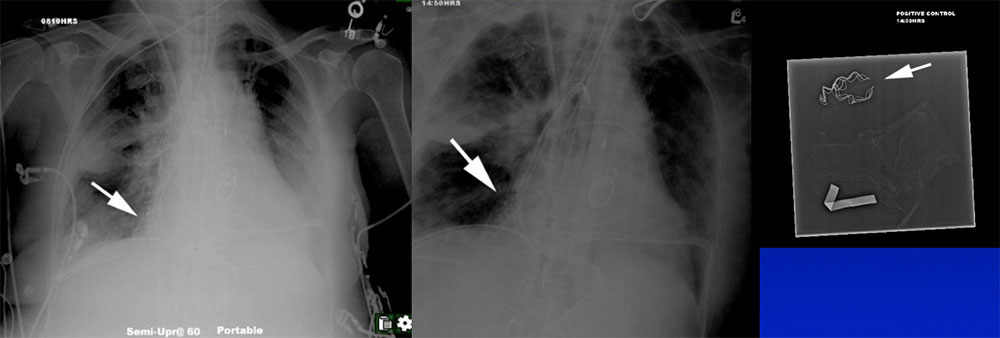

Case 10  Chest radiograph on a 48 year old man shows:

Case 10  Chest radiograph on a 48 year old man shows:

Wireless capsule pH monitoring device